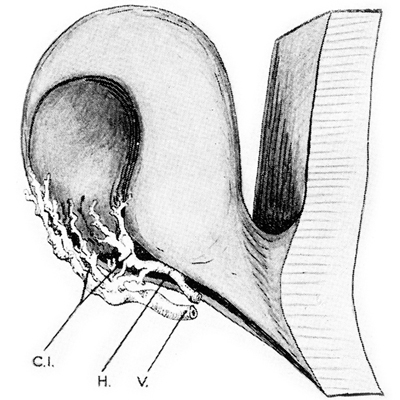

Dibujo de vaso persistente produciendo muesca en el borde de la copa

Foto tomada de: Ida Mann; The development of the Human Eye. 1969. Grune & Straton Inc N.Y

Dibujo de vaso persistente produciendo muesca en el borde de la copa

Embrión humano de 2 meses

Las posibles explicaciones de su origen siguen en discusión y la pregunta es: ¿la causa primaria de los colobomas es Ectodémica o Mesodérmica? Podría tratarse de una falla localizada en una porción del margen ectodérmico de la copa óptica o bien, a una persistencia indebida del mesodermo fetal, que secundariamente inhibiría el crecimiento del ectodermo en contacto con él.

Existen múltiples argumentos relacionados, pero ninguno definitivo. actualmente se habla más de los errores genéticos que pueden producir estos defectos.